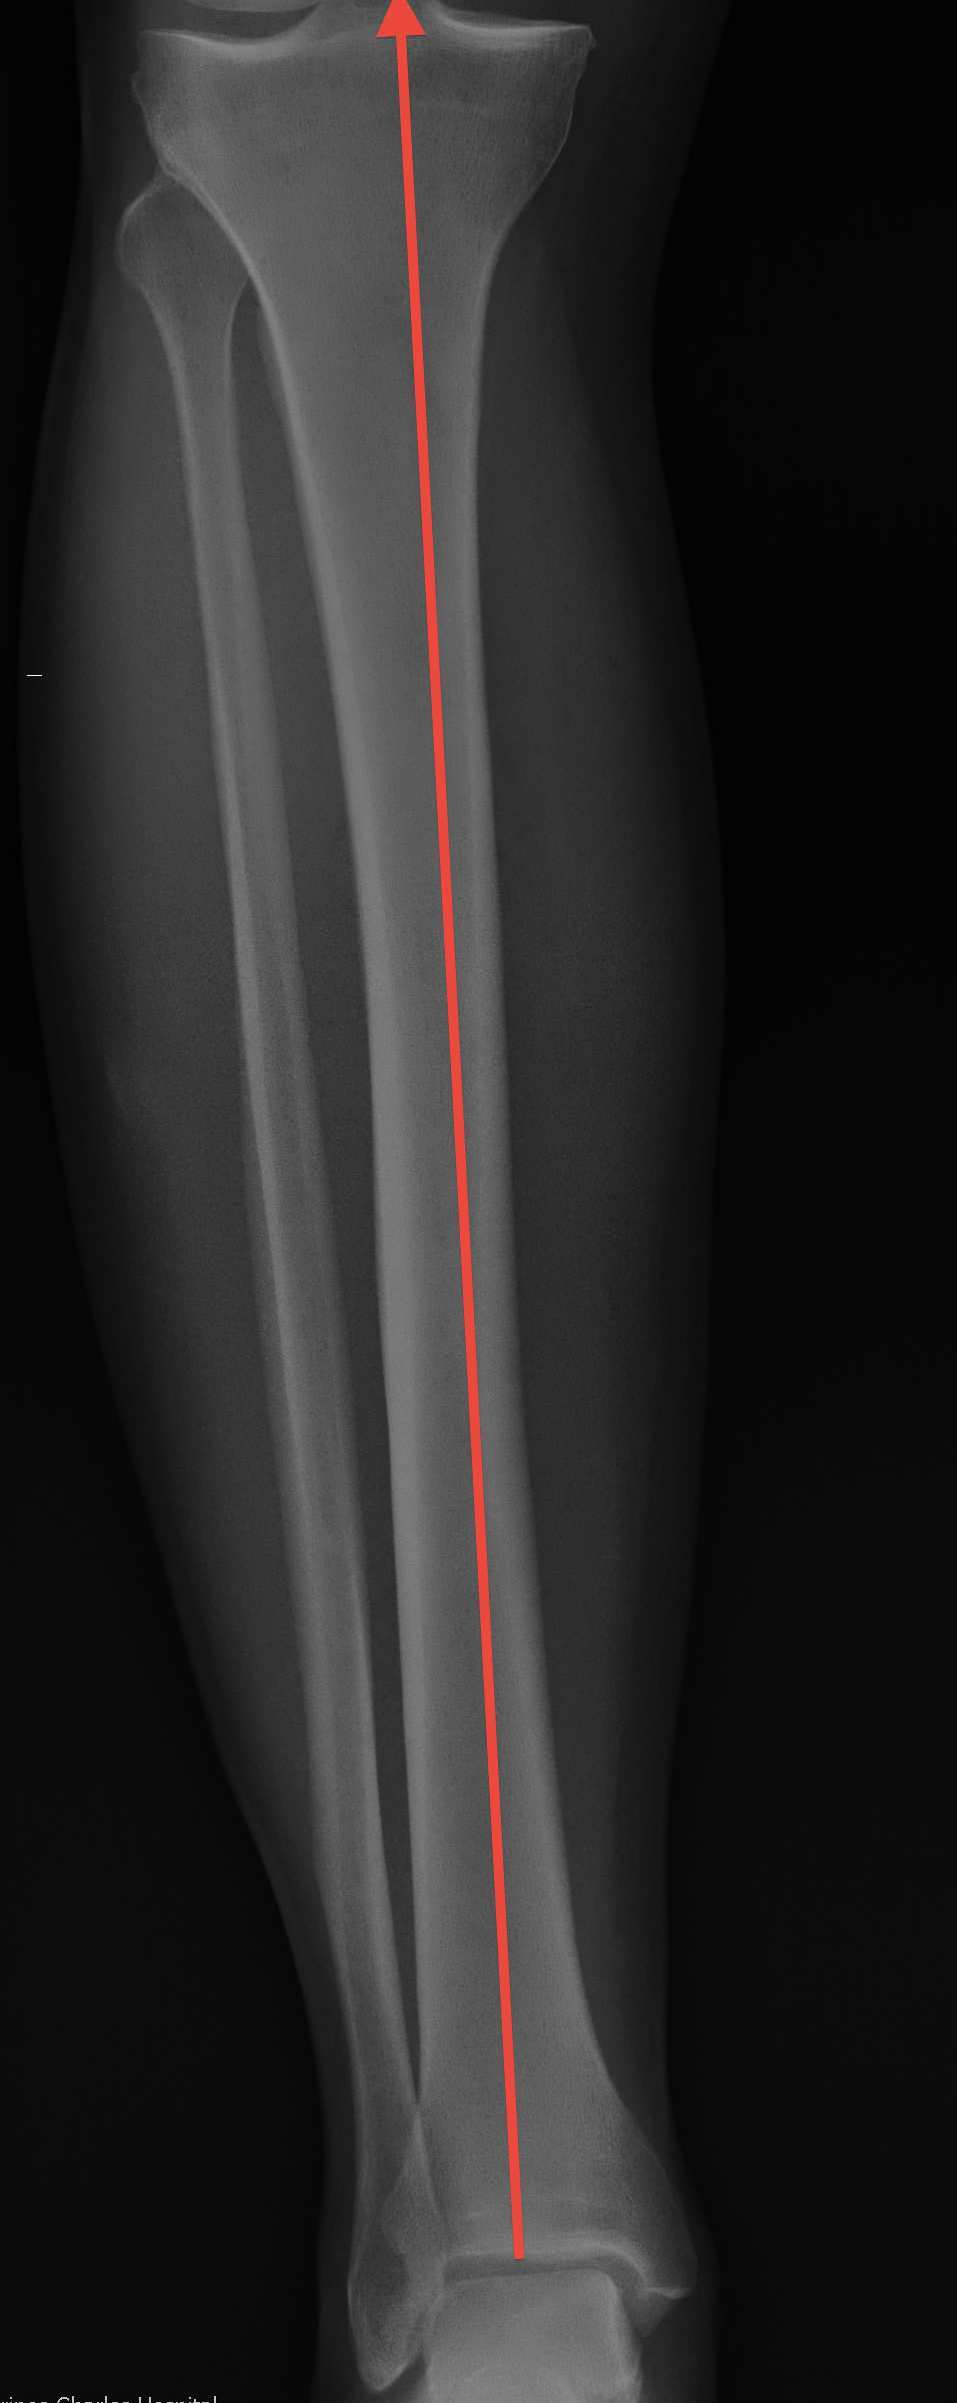

MPTA (medial proximal tibial angle) |

| 3o valgus relative to MA | 81o | 87o | 87o or 3o varus | 9° |

| 6o valgus distal femur | ||||

| 3o varus proximal tibia |